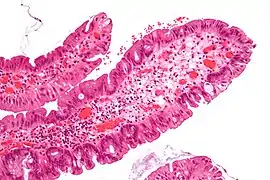

| Villous adenoma | 15%[16] to 40%[15] | Over 75% villous[14] | ![]() | |

The villous subdivision is associated with the highest malignant potential because they generally have the largest surface area. (This is because the villi are projections into the lumen and hence have a bigger surface area.) However, villous adenomas are no more likely than tubular or tubulovillous adenomas to become cancerous if their sizes are all the same.[18]

- Villous adenoma: 40% risk of cancer

Micrograph of a villous adenoma. These polyps are considered to have a high risk of malignant transformation. H&E stain.